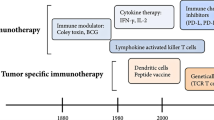

Due to the vast heterogeneity of OS molecular profiles [35,36,37,38,39,40, 63, 64], the future of OS treatment may be moving away from targeted anti-oncogenic paradigms and toward more generalized immunomodulatory/immunoeditory approaches [156]. Cancer immunotherapy, although still in its infancy, attempts to enhance tumor immunogenicity and stimulate tumorocidal activity, thereby reallocating the burden of disease clearance back to the patient’s own body. Nonspecific immunogens, cytokines, adoptive T-cells, vaccines, oncolytic virotherapies, and checkpoint blockades have all shown potential therapeutic promise [157]. If deemed clinically advantageous, these new immunotherapeutics will likely be administered as adjuvants and integrated into the current standard of care.